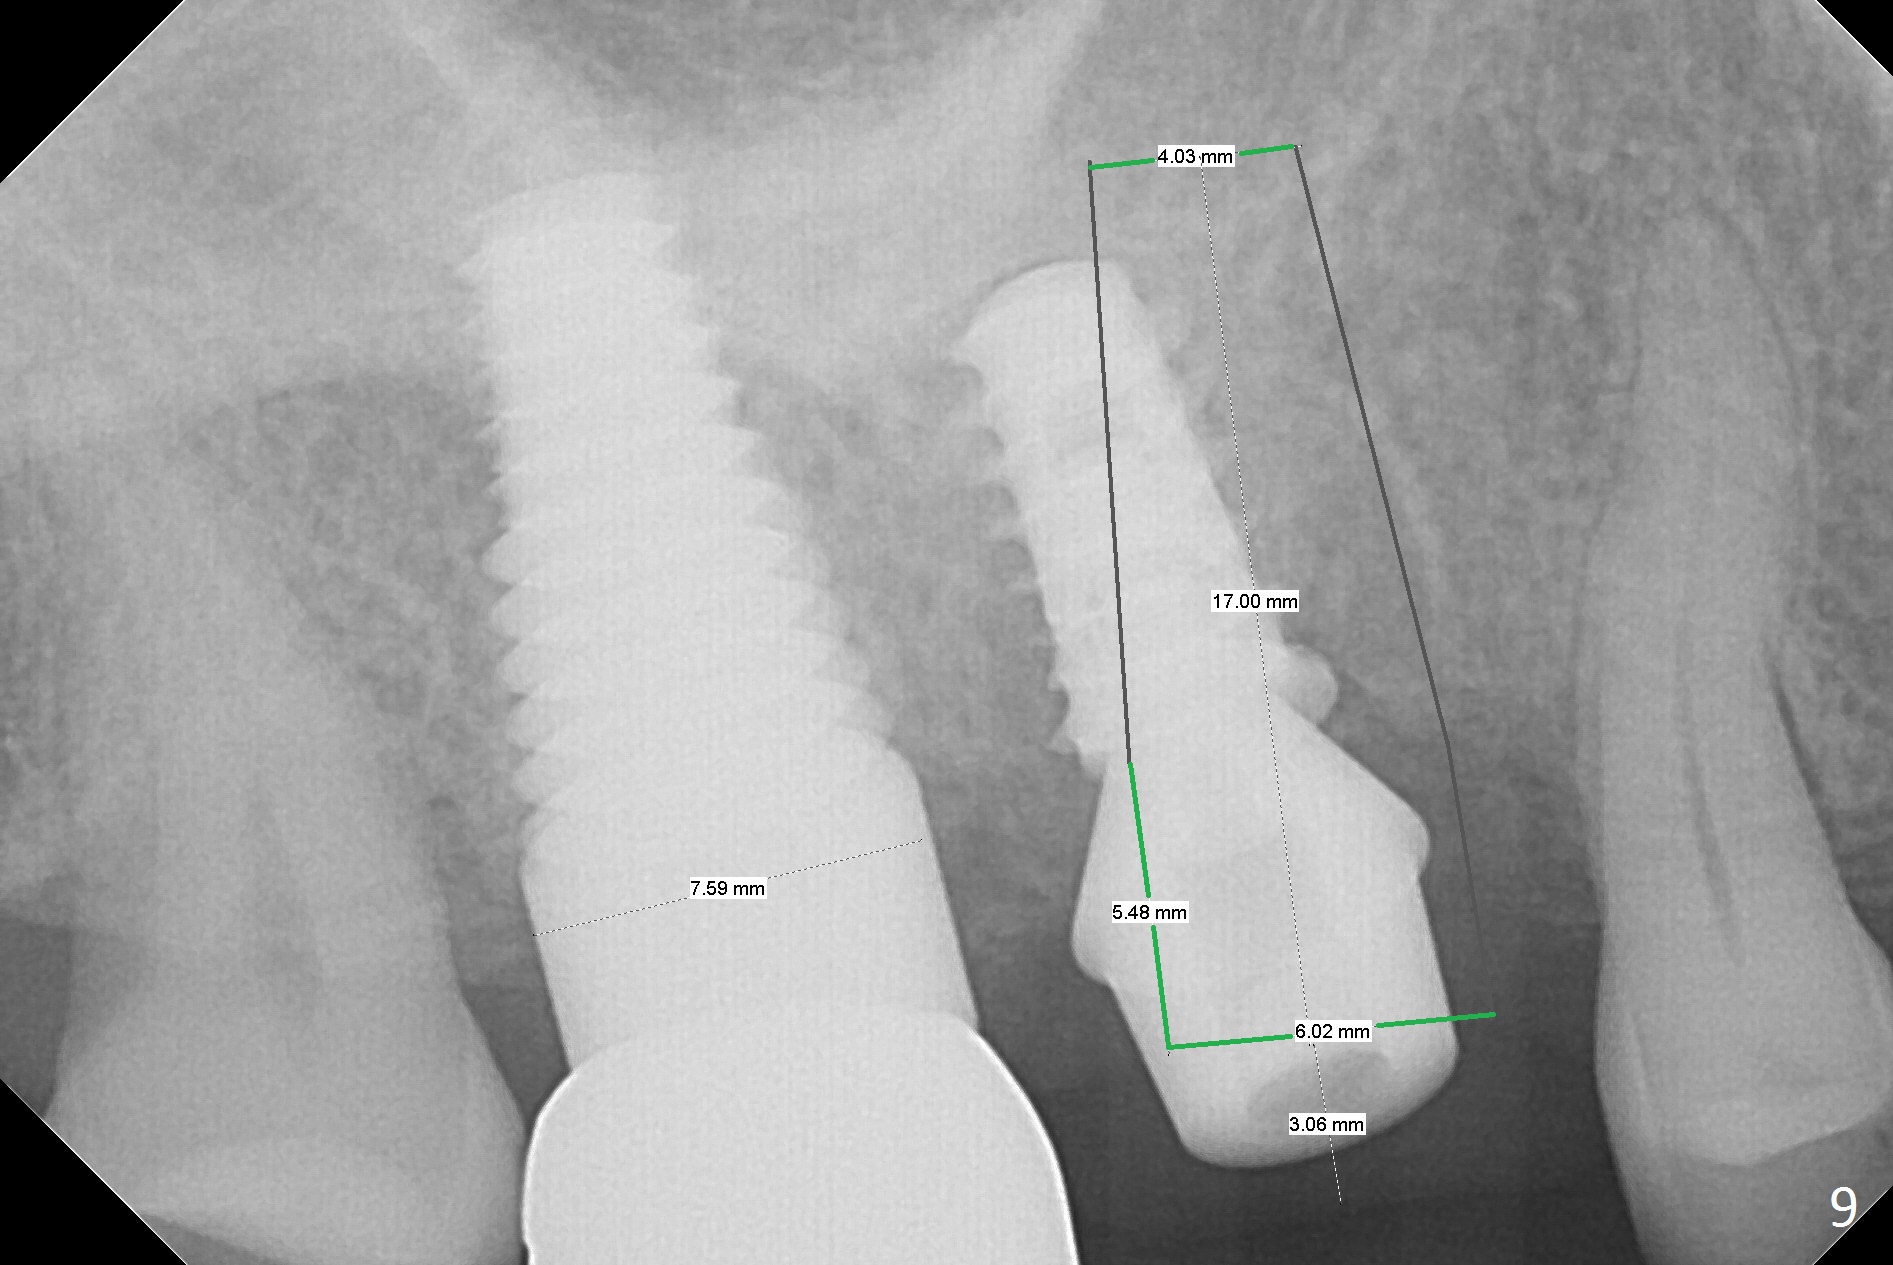

Heavy bruxism is characterized by the crack at #3 (symptomatic, requiring emergency extraction) and loss of the palatal cusp at #5 (Fig.1). Osteotomy is initiated in the septal slope (Fig.2 S) with a 1.6 mm pilot drill for 9 mm (with sudden empty feeling), followed by Marking bur. After 4.3 mm Magic Drill is used for ~ 9 mm, the sinus membrane is found to perforate. A dummy implant (5x9 mm, 2 mm shorter than design) is placed short of the sinus floor (Fig.3 ^). Prior to placement of 5.5x9 mm IBS implant (~ 35 Ncm, Fig.4,5), a piece of Osteogen plug is inserted into the osteotomy for repair of the perforation. The final implant is also shy of the sinus floor (Fig.5 ^). The Osteogen plug is apparently placed underneath the sinus floor so that it should be able to repair hard and soft tissue defects. The remaining sockets are mainly filled with Osteogen plug, while the implant plateau is covered by autogenous bone and Osteogen. When a 6.5x4(3) mm abutment is placed, an immediate provisional is fabricated (Fig.6) with its margin placed subgingival (Fig.6 inset dashed line). This innovative design of the provisional is to prevent collapse of the most coronal gingiva and loss of bone graft, particularly where the bony plate is defective. Although there is mild pain postop, nasal hemorrhage or discharge is absent.

The patient returns with chief complaint of crown is loose with pain 3 months postop (Fig.7). Under local anesthesia, the provisional is removed. The gingiva is erythematous. The implant has mobility. A healing abutment is placed (6x2 mm). One month later, the implant remains unstable. The patient is scheduled to return 3.5 months postop to either retighten the implant with healing screw or replace with a 6x17 mm Tatum implant (Fig.9) after changing trajectory (Fig.8 red arrow).